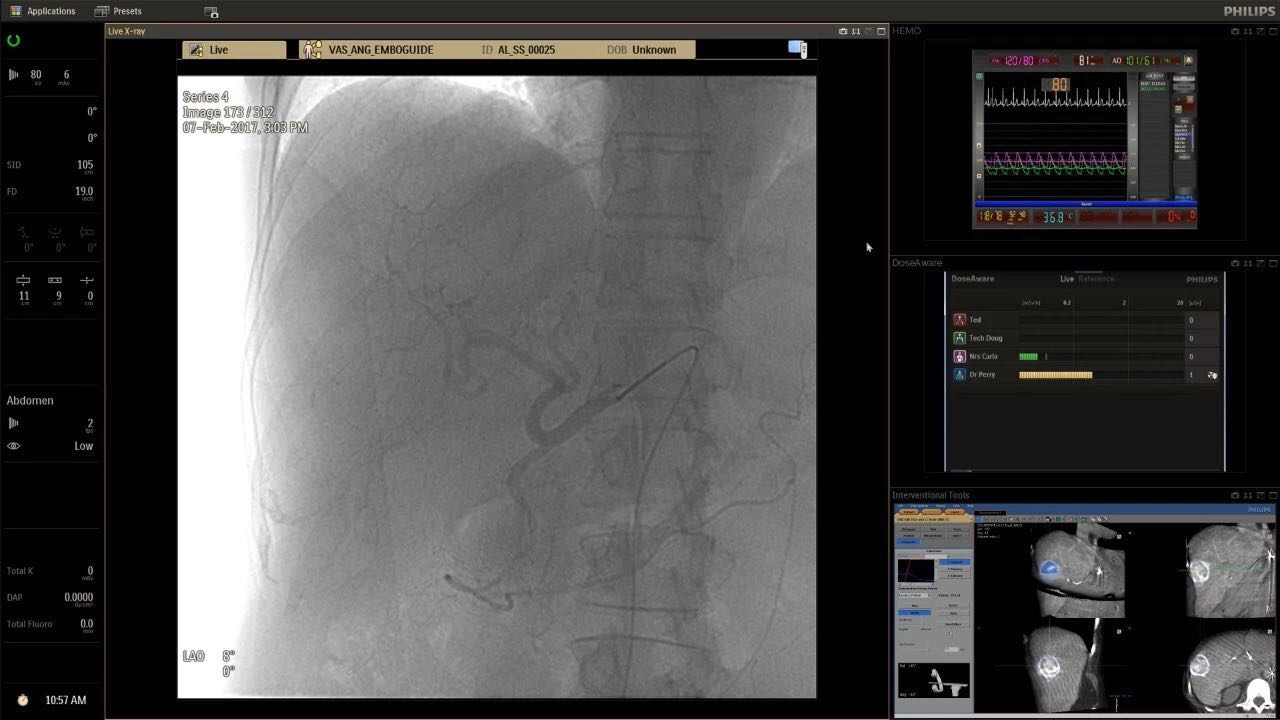

在日益復(fù)雜的干預(yù)期間,臨床醫(yī)生需要快速、輕松地可視化關(guān)鍵解剖結(jié)構(gòu)并確定手術(shù)過(guò)程中患者的變化。2019年1月17日,飛利浦宣布推出采用FlexArm的Azurion 7 C20,旨在提高圖像引導(dǎo)程序的定位靈活性。

帶有FlexArm的Azurion 7 C20 包含一系列創(chuàng)新技術(shù),使臨床醫(yī)生可以更輕松地在整個(gè)患者身上進(jìn)行二維和三維成像。當(dāng)臨床醫(yī)生移動(dòng)系統(tǒng)時(shí),圖像光束自動(dòng)保持與患者的對(duì)準(zhǔn),允許更一致的可視化并使他們能夠?qū)⒆⒁饬性谥委熒稀?/span>

可通過(guò)微創(chuàng)手術(shù)治療的疾病的范圍和復(fù)雜性繼續(xù)擴(kuò)大。相應(yīng)地,程序本身也變得更加復(fù)雜,需要來(lái)自不同學(xué)科的更多醫(yī)生在患者的桌邊,以高度協(xié)調(diào)的方式一起工作。因此,臨床團(tuán)隊(duì)需要在高度受限的環(huán)境中執(zhí)行越來(lái)越具有挑戰(zhàn)性的程序。

飛利浦表示,采用FlexArm設(shè)計(jì)的Azurion 7 C20可提供卓越的靈活性和直觀的控制。該系統(tǒng)由智能運(yùn)動(dòng)引擎驅(qū)動(dòng),可在八個(gè)不同的軸上移動(dòng),所有這些軸均由其單個(gè)“Axsys”控制器控制。臨床醫(yī)生的模擬測(cè)試表明,該系統(tǒng)有可能顯著減少患者,工作人員和設(shè)備的重新定位,從而改善微創(chuàng)手術(shù)的可及性,包括通過(guò)患者手腕進(jìn)入身體的手術(shù)(橈動(dòng)脈入路),并降低患者的風(fēng)險(xiǎn)。無(wú)意中拔出電線和管子,以及節(jié)省大量時(shí)間。該系統(tǒng)非常適合混合手術(shù)室(OR),可滿足一個(gè)房間內(nèi)的多種專業(yè)需求,例如手術(shù)和血管內(nèi)手術(shù)的組合。